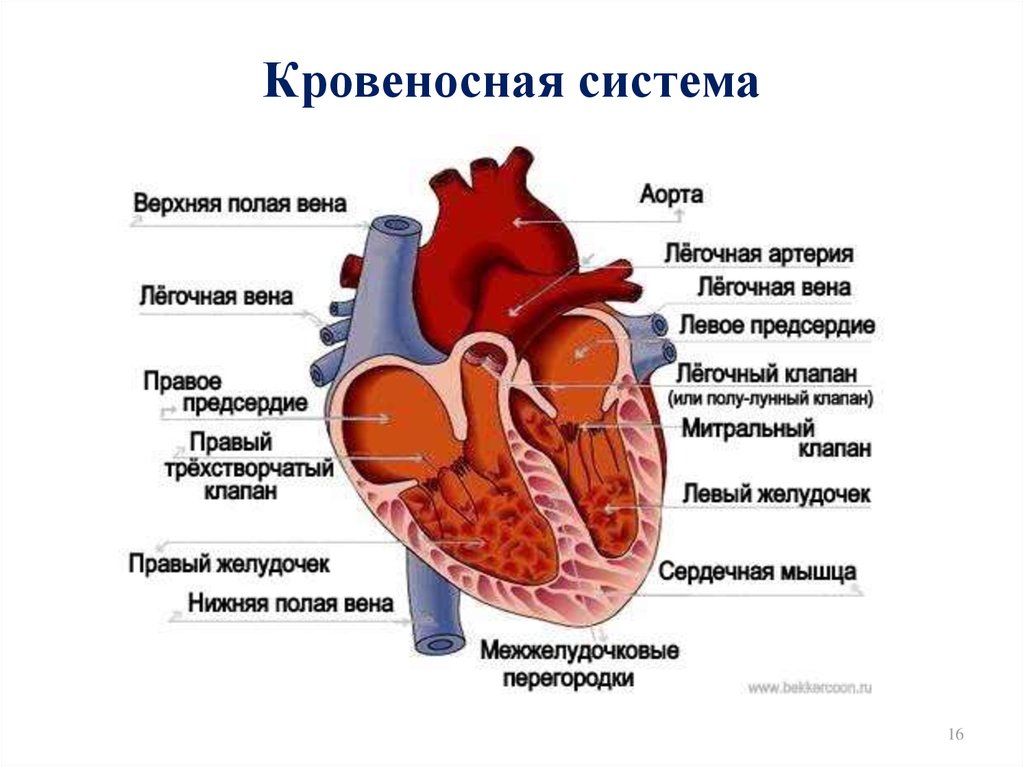

Анатомия человека: кровеносная система и её связь со скелетом